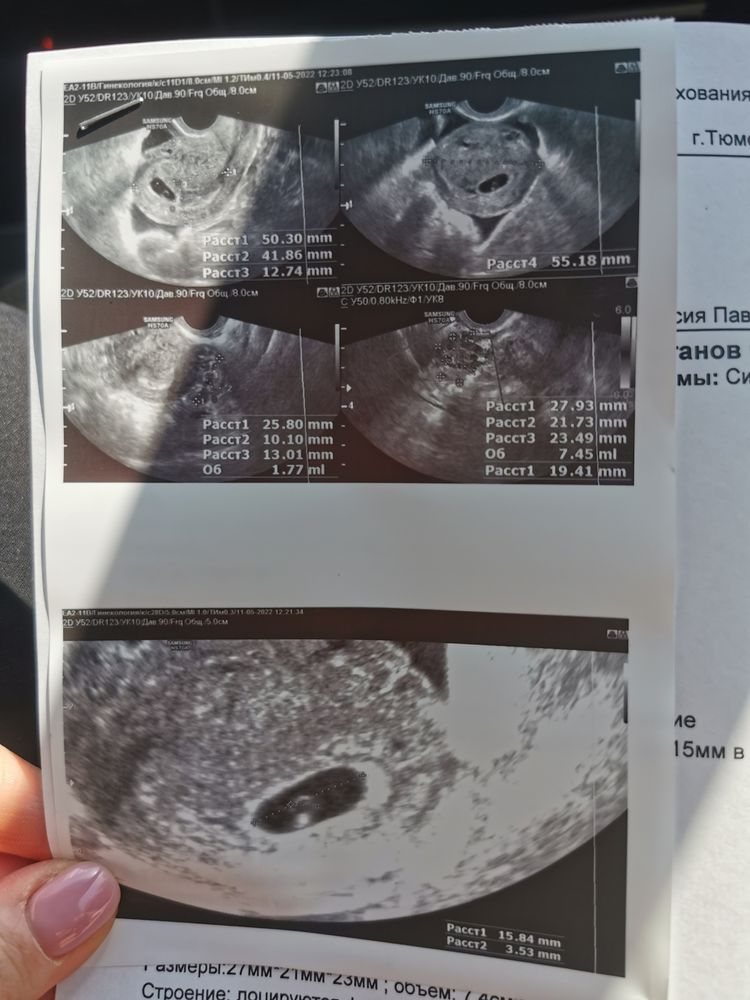

Размер плодного яйца на срок 6 недель - 15 мм

Желточный мешок - 3.5 мм

Желтое тело - 19 мм